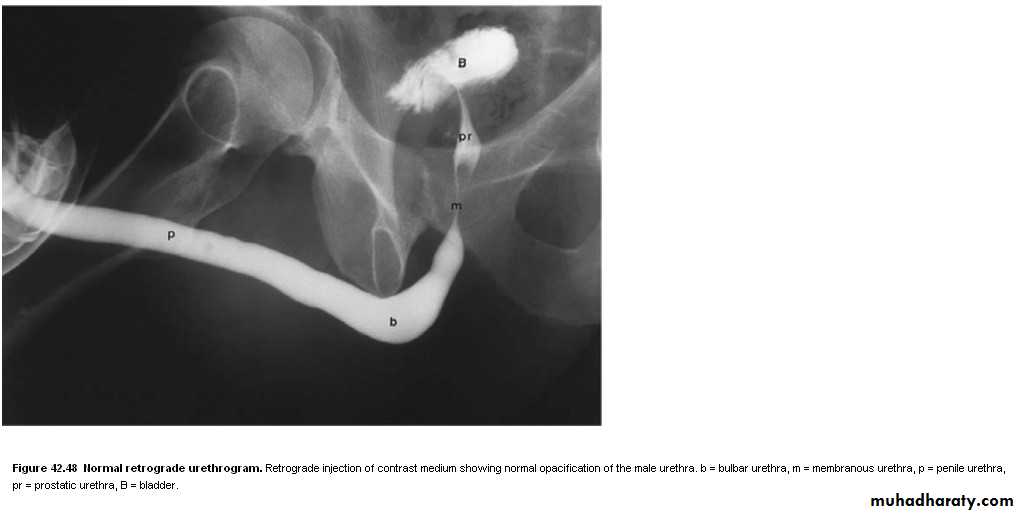

Ascending urethrogram

used mainly for diagnosis of urethral strictureRetrograde & antegrade pyelography

• Congenital valves in the posterior urethra in boys are the commonest cause of bladder outflow obstruction in male children. The diagnosis may be first suspected at antenatal US, where there is bilateral hydronephrosis. After birth, US confirms bilateral hydronephrosis and hydroureters and a thick-walled bladder. Urethral valves cannot be demonstrated by retrograde urethrography as there is no obstruction to retrograde flow. They are easily demonstrated at micturating cystourethrography, where substantial dilatation of the posterior urethra is seen which terminates abruptly in a convex border formed by the valves.Urethral strictures